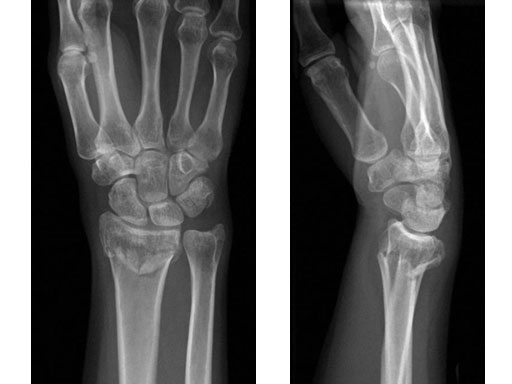

36-year-old female fell down on a meadow.

Case provided by Ladislav Nagy, Zrich, CH

Fig 1ab Preoperative x-rays.